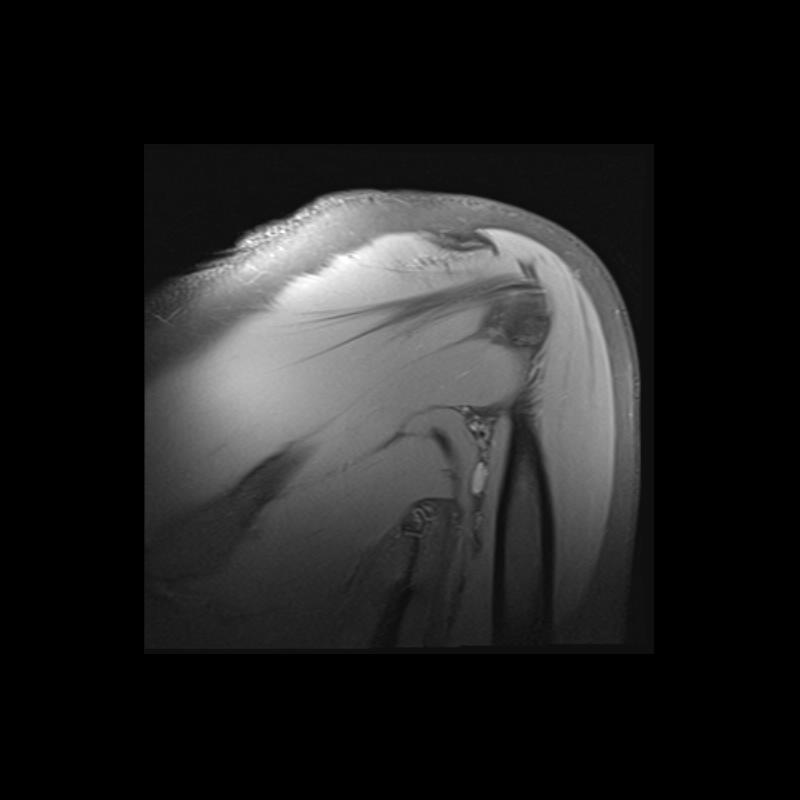

Shoulder MRI Anatomy